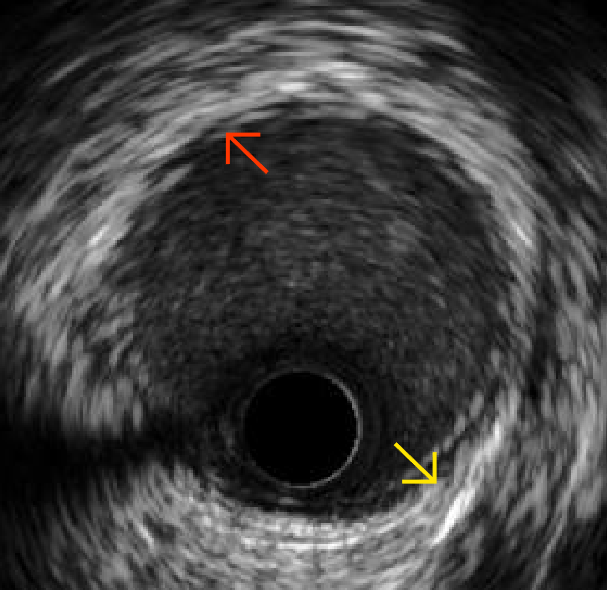

血管内超声机器 IVUS下显示的正常血管内部形态

近年来IVUS作为新的冠状动脉病变诊断手段,它除了可显示管腔形态外,还可清晰显示血管壁,初步确定粥样硬化斑块的组织形态学特征;同时,通过准确的定量分析,测量血管直径、横截面积和狭窄程度,可识别冠状动脉造影不能发现的早期动脉粥样硬化病变,尤其对冠状动脉造影显示的临界病变,IVUS可对其进行精确的定量分析,确定其狭窄程度及病变类型,以协助临床治疗方案的选择。IVUS是冠脉造影的完美补充,更能全面了解冠脉病变情况,更好为术者提供临床指导,从而为患者提供最佳、最安全的治疗决策。

通过血管内超声(IVUS)测量可以得到

黄色外弹力膜面积及其最大/最小直径

蓝色有效管腔面积及其最大/最小直径

红色最大/最小斑块厚度并可进一步计算出斑块面积和厚度以及偏心指数等